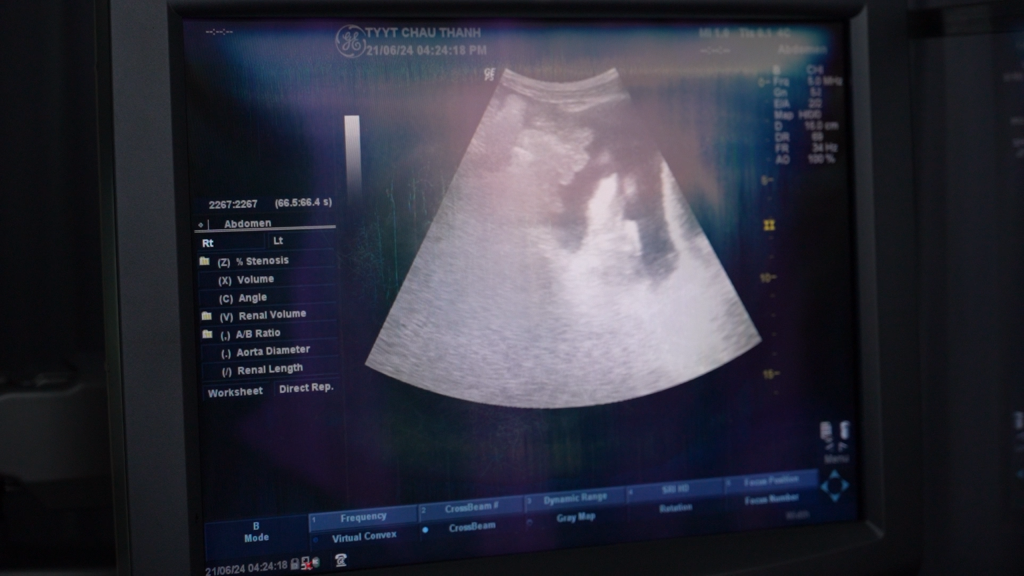

Tăng cường đầu tư cơ sở vật chất cho y tế cơ sở